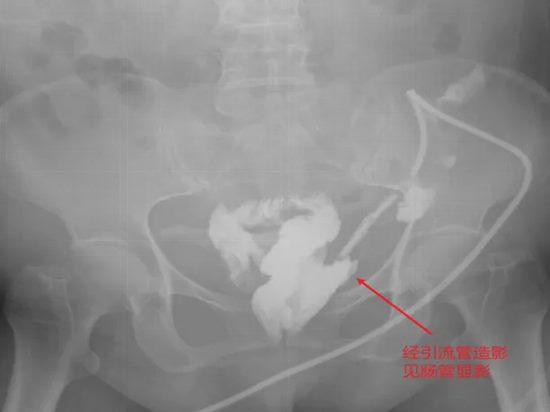

病例七:四次清创仍找不到瘘口?一场“侦探式”的寻瘘之旅

病情简述:患者胰十二指肠术后并发胆瘘、胰瘘、肠瘘,外院四次清创仍无法控制,瘘口位置不明。

诊疗破局:明确诊断是治疗的起点。团队通过精心设计的多次、多途径造影检查,最终精准定位瘘口位于结肠肝区。明确“敌情”后,先通过营养支持稳住“阵地”,再行回肠造口转流,为后续治疗创造了条件。

技术体现:在复杂的术后并发症中,“诊断先行”的思维是个体化序贯治疗的核心。